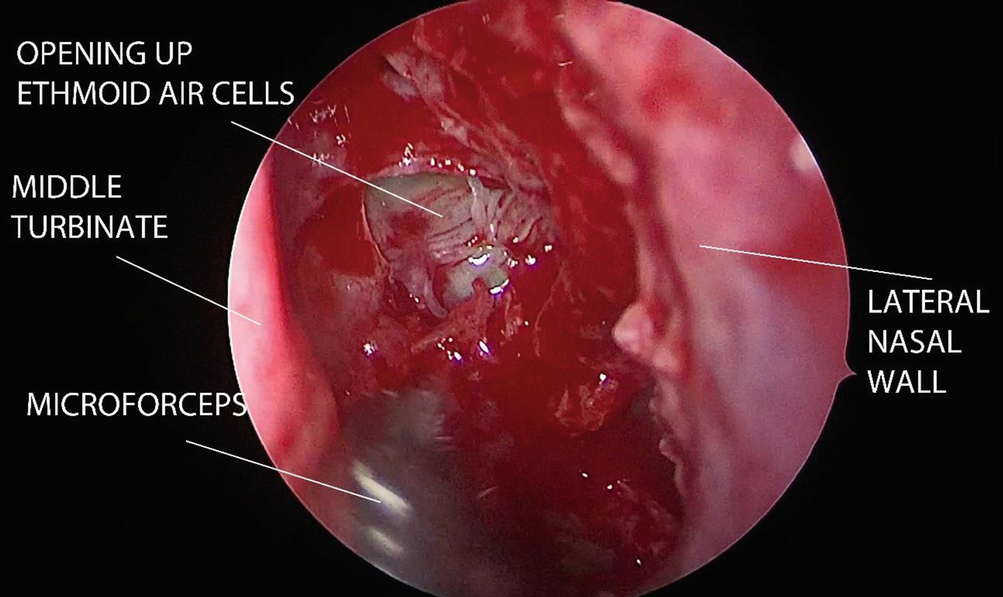

The anterior ethmoid air cells are opened up with a straight Blakesley forceps and removed in piecemeal fashion. Posterior ethmoidectomy is done by penetrating the basal lamella with ball probe at its medial and inferior part. Posterior ethmoid cells are then removed by either blunt curette or straight Blakesley forceps (Fig. 12.4).

../images/481431_1_En_12_Chapter/481431_1_En_12_Fig4_HTML.png

Fig. 12.4

Ethmoidectomy is done whereby the anterior and posterior ethmoid air cells are opened up